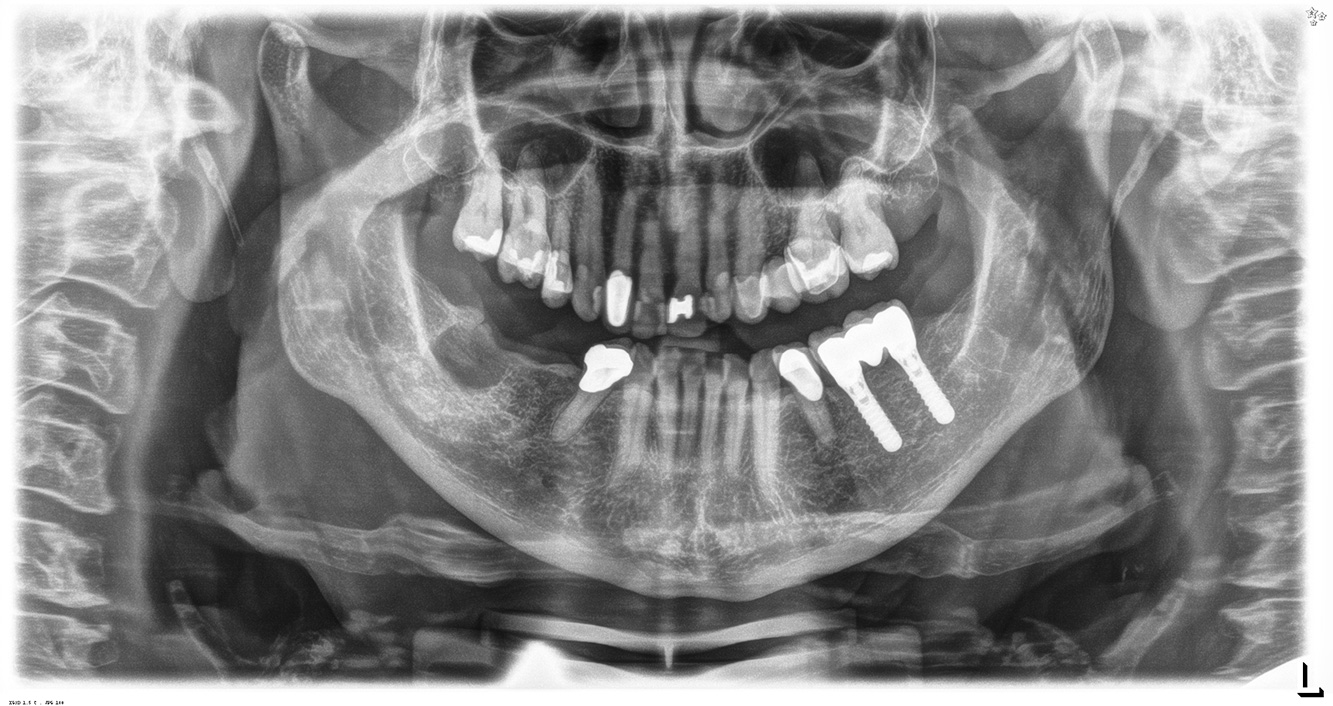

In the medical history, the 55-year-old patient states that he has no systemic disease and is not taking any medication. The patient’s lifestyle is similarly unremarkable. The patient has a few tooth restorations and two implants (2nd and 4th quadrants). On the basis of current findings, gingivitis is identified in an otherwise stable periodontal condition on the reduced periodontium (stage III, grade A). more

The healthy patient with pre-existing periodontal disease & peri-implantitis

A 52-year-old patient presents at a preventive care session. The patient has no systemic disease and is not taking any medication. He has had various dental treatments and also has two active carious lesions. In addition, the patient has four implants (2nd, 3rd and 4th quadrants). He is revealed to have early periodontal disease (stage IV, grade B). His periodontal condition is stable; a probing depth of Probing depths (ST) of 5 mm is only evident at the implant in region 36. Gingivitis is also identified. more

The healthy patient with early periodontal disease

The 68-year-old patient has no general health conditions and is not taking any medication that may be relevant to her oral health, and her lifestyle does not pose any particular risk. The patient has two dental implants (3rd quadrant, for five years) and a previous case of periodontal disease (stage IV, grade B periodontitis) with tooth loss. Currently the periodontal conditions are stable. However, periodontitis significantly increases the biological complications of implantations and there is a risk of implant loss (21). Four recommendations can be determined for the prophylaxis session. more